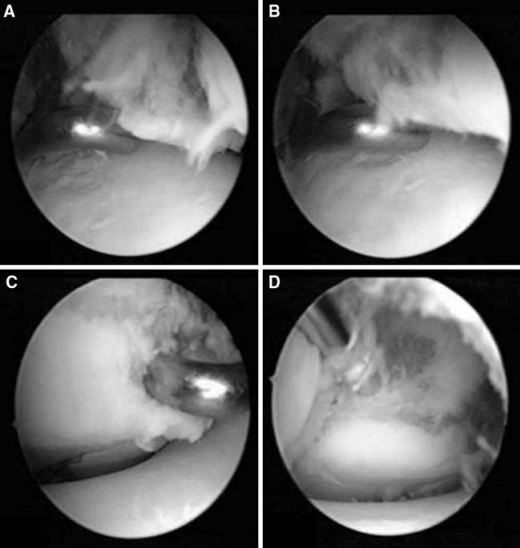

关节镜辅助下复位固定。A(踝关节镜前内侧入路)见到骨折部位移位,影响关节匹配性。B(踝关节镜前内侧入路)使用探钩复位骨折块。C(踝关节镜前外侧入路)确认骨折块复位。D(踝关节镜前外侧入路)在关节镜监视下经皮打入克氏针。图源:DOI: 10.1007/s00167-006-0234-3.